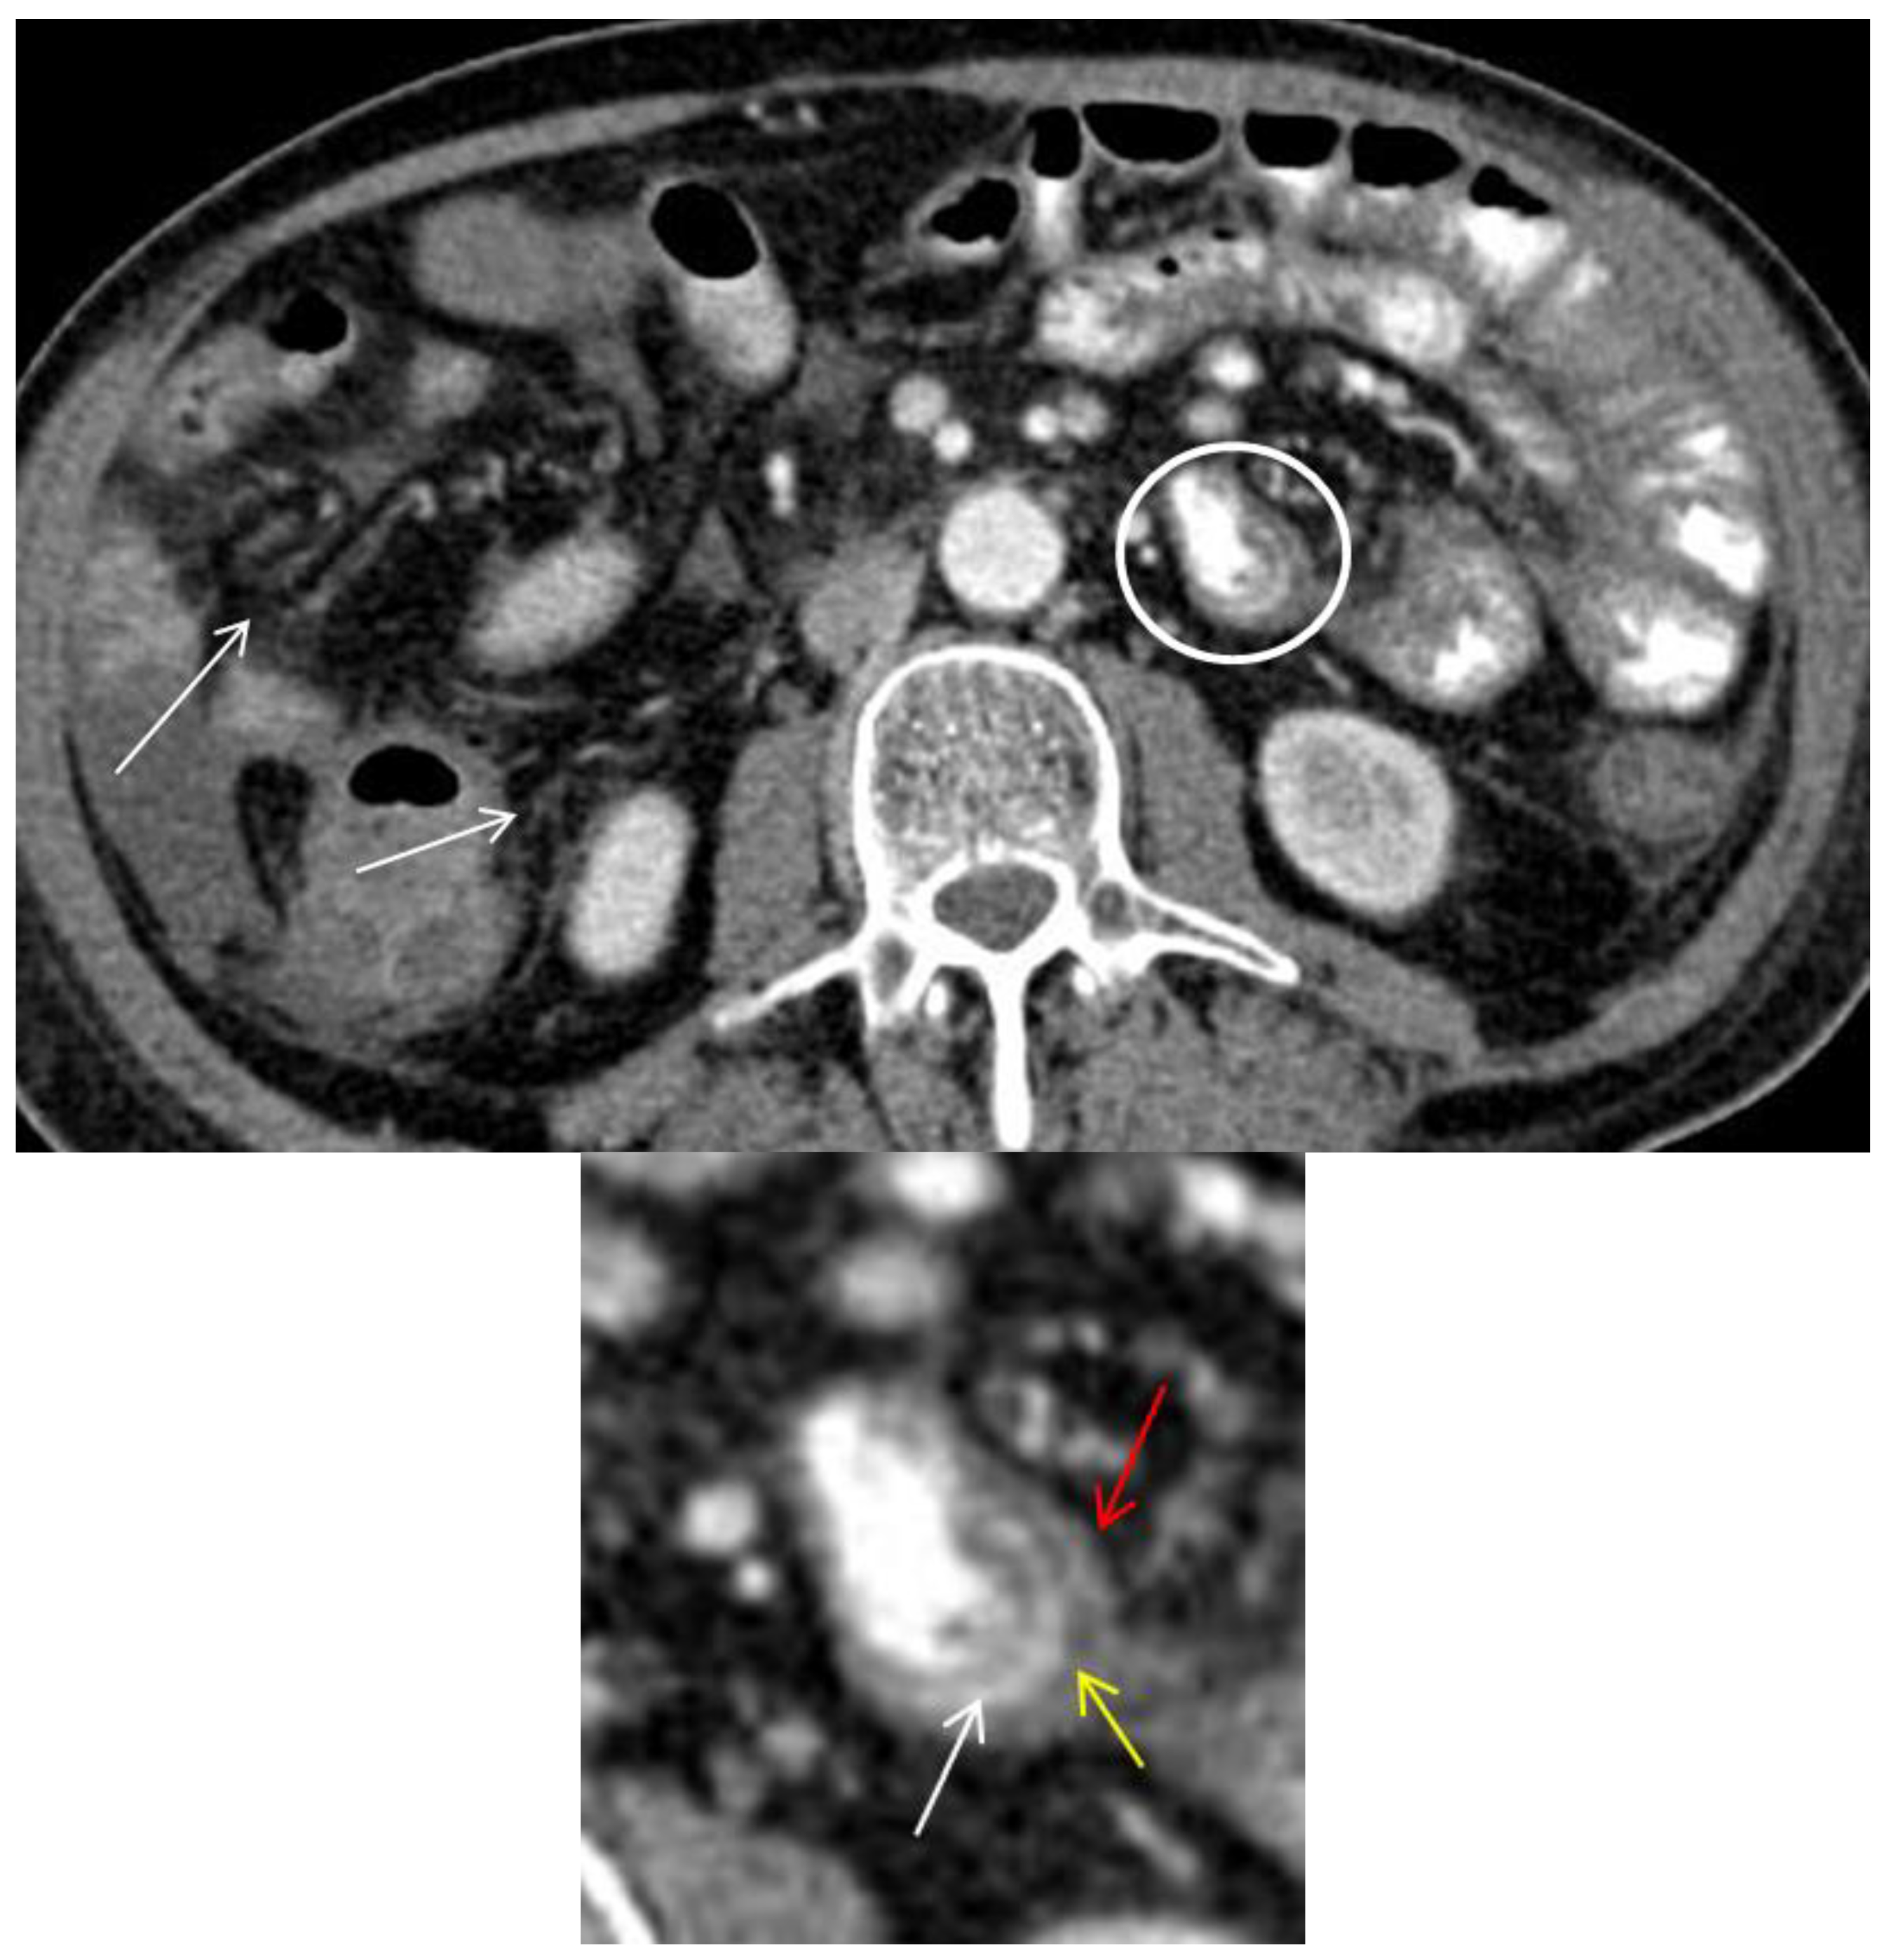

Axial CT image shows circumferential small bowel wall thickening (>3 mm) with trilaminar mural stratification in the small-bowel (circle and magnified image) with serosal enhancement (red arrow), low intramural attenuation (yellow arrow) and mucosal enhancement (white arrow) [2,13]. Low intramural attenuation can represent edema, inflammatory infiltrate or fat [13]. Stranding of the mesenteric fat is often observed in GIT-GVHD [2,6] (arrows). Mural stratification is a non-specific sign of bowel inflammation and has been shown to correlate with clinically active disease as opposed of a more homogenously enhancement due to fibrosis [14,15]. In this patient, three different patterns of mural stratification and mural enhancement were present in separate segments (Figure 2 and Figure 3).